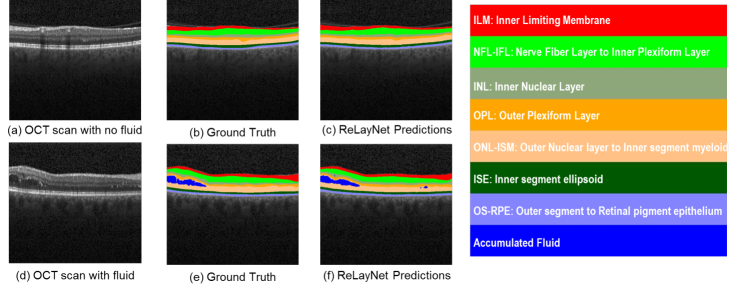

Towards this end, we propose a deep learning based end-to-end learning framework for segmentation of multiple retinal layers and delineation of fluid pockets in eye OCT images, called ReLayNet (short for Retinal Layer segmentation network). To the best of our knowledge, this is the first time deep learning based fully convolutional end-to-end method leveraged towards this application. Figure 1 previews the results of the proposed ReLayNet for two OCT slices (without and with fluid mass).

Refer to caption

Fig. 1: Segmentation results of the proposed ReLayNet of OCT frames without and with fluid mass. OCT frame without fluid, its ground truth and ReLayNet segmentation are shown in (a), (b) and (c) respectively. OCT frame with fluid, its ground truth and RelayNet predictions are shown in (d), (e) and (f) respectively. The retinal layers and fluid corresponding to each colors are presented to the right.

Given a retinal OCT image \mathcal{I}, the task is to assign each pixel location 𝐱=(r,c)𝐱𝑟𝑐\mathbf{x}=(r,c) to a particular label l𝑙l in the label space ={l}={1,,K}𝑙1𝐾\mathcal{L}=\{l\}=\{1,\cdots,K\} for K𝐾K classes. We treat the current segmentation task as a K=10𝐾10K=10 class classification problem. The tissue classes include 7 retinal layers illustrated in Figure 1, Region above the retina (RaR), Region below RPE (RbR) and accumulated Fluid.